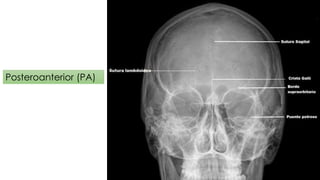

Este documento describe diferentes tipos de proyecciones radiográficas craneales, incluyendo laterales, posteroanteriores y anteroposteriores, que permiten examinar estructuras óseas y blandas del cráneo. También menciona que las proyecciones axiales permiten ver órbitas, senos paranasales y cornetes, y que los estudios con contraste pueden identificar aneurismas cerebrales y malformaciones arteriovenosas.